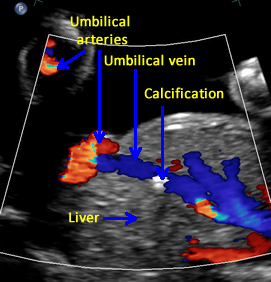

Above. Gestational age is 23 weeks. Isolated hepatic calcification. The calcification measures 4.2 x 7.4 x 6.9 mm. It is adjacent to the hepatic vein.

Above. Gestational age is 23 weeks. Isolated hepatic calcification. Color Doppler demonstrates the relationship of the echogenic focus to the hepatic vein. The lesion was not within the gallbladder and there were no adverse outcomes.